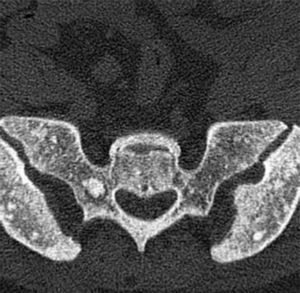

En un control radiográfico rutinario de la columna lumbar (fig. 1), se observan numerosos focos pequeños, bien definidos, homogéneos, circulares, de mayor densidad ósea, en los cuerpos vertebrales, a lo largo de todo el esqueleto axial, por lo que se amplía estudio con radiografía de pelvis AP (fig. 2) y TAC de pelvis y cuerpo vertebral lumbar (figs. 3 y 4), que mostraban lesiones radiodensas redondeadas u ovales en la cabeza y el cuello femorales y en regiones pertrocantéreas, con presencia de pequeñas áreas de densidad aumentada en la pelvis y en los cuerpos vertebrales que indicaban como primer diagnóstico osteopoiquilia. No se observaban componente de partes blandas, ni áreas de rotura de la cortical, ni presencia de reacciones periósticas de características agresivas.